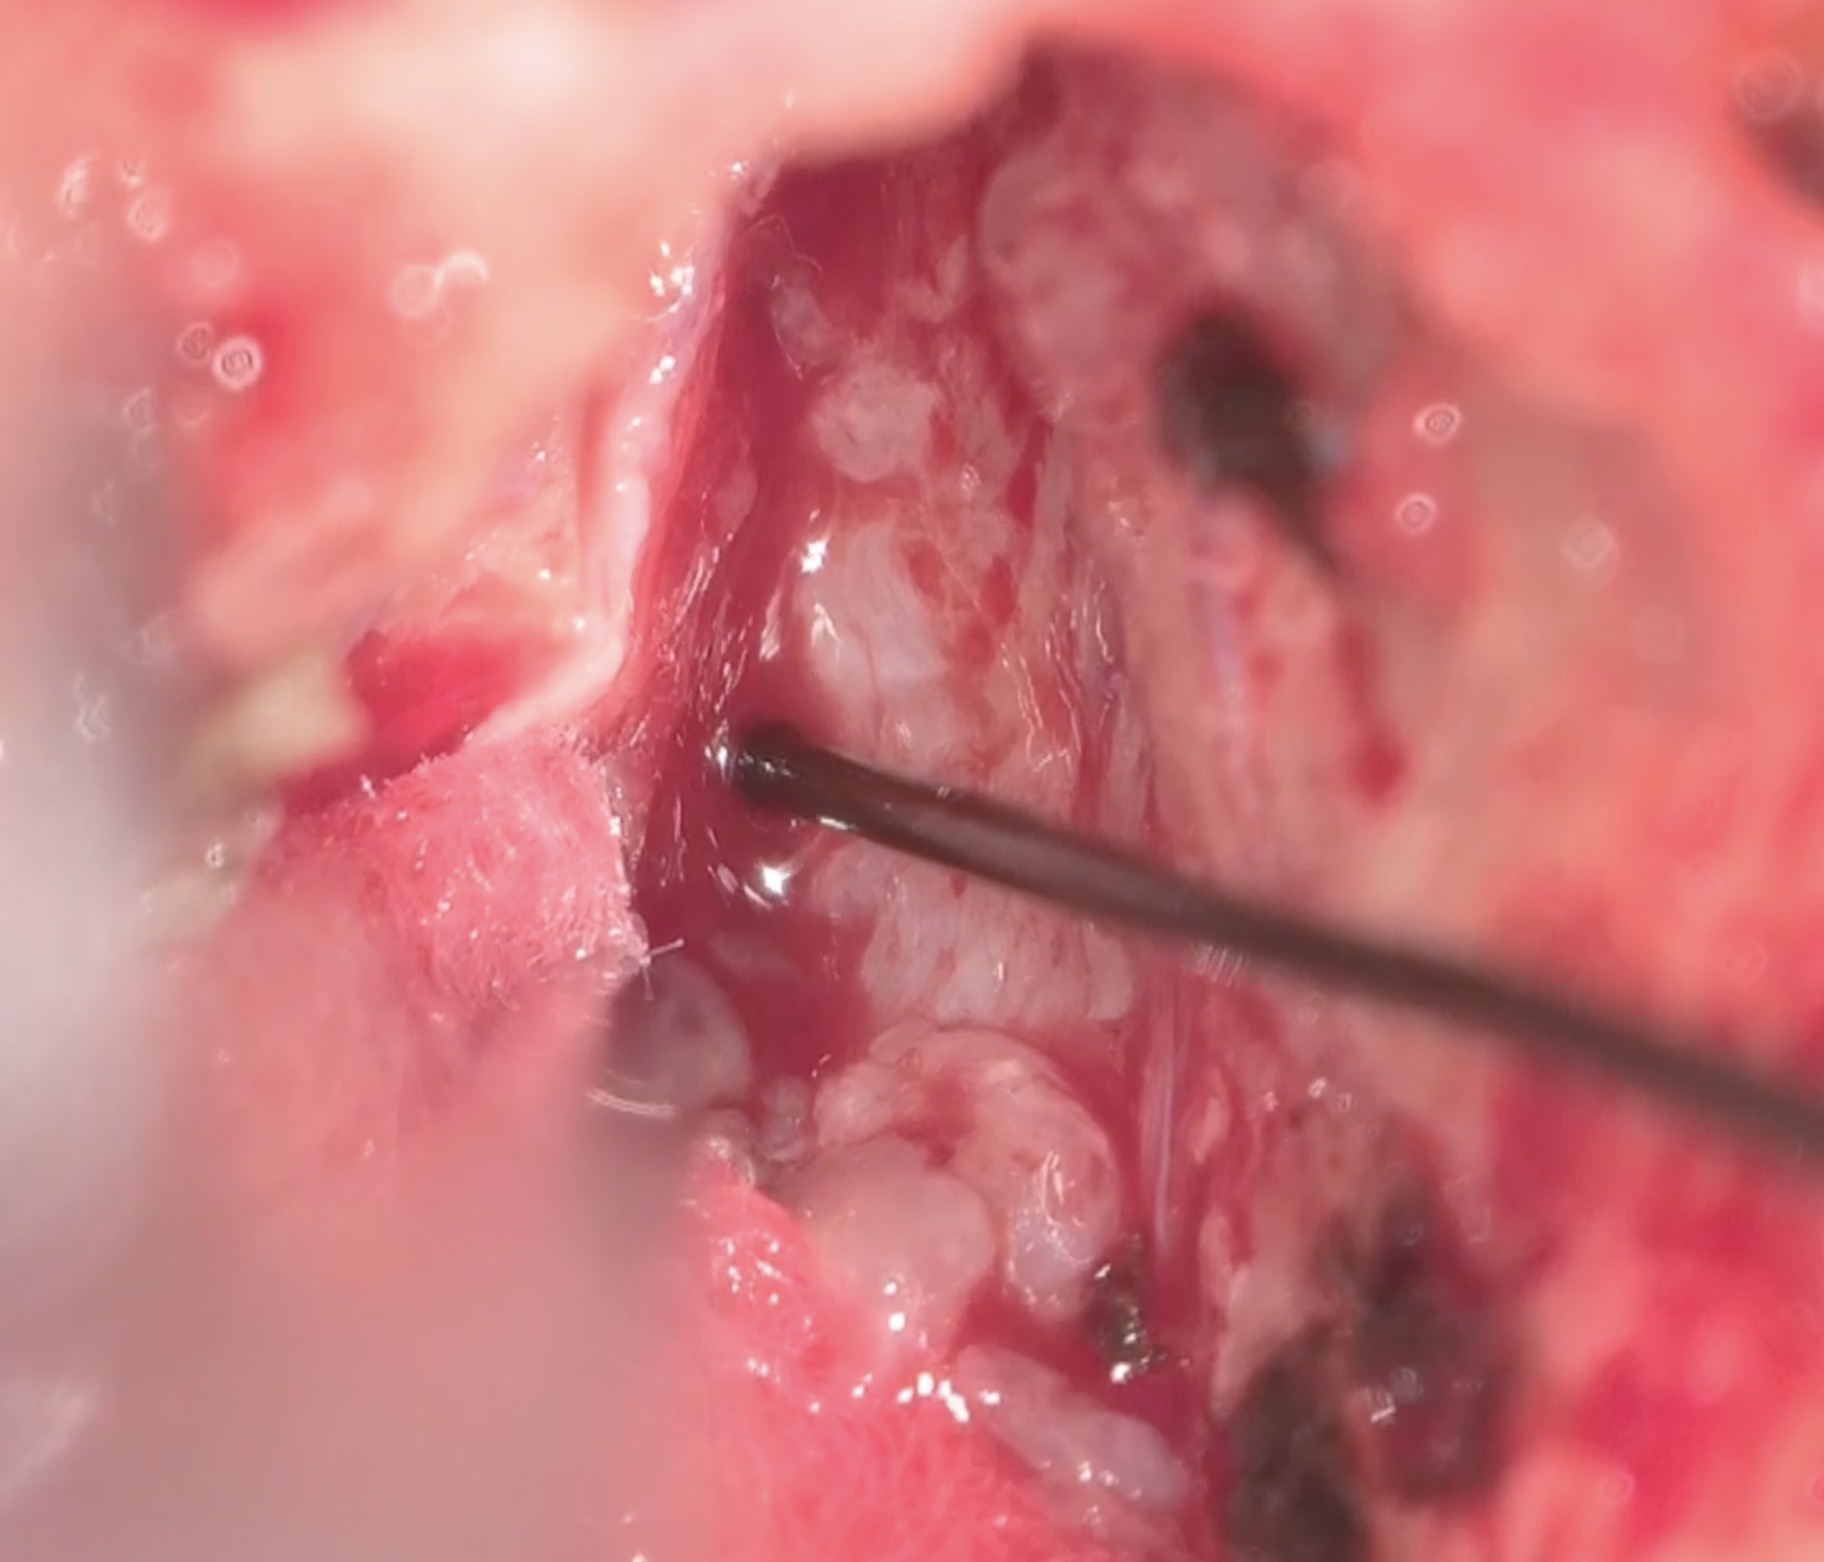

手術は通常通り行われ、顔面神経の麻痺を起こさずに摘出は終了し、うまくいったと考えていました。しかし術後より覚醒障害が続き、強い小脳腫脹を生じたため、術後脳室ドレナージ術、バルビタール麻酔療法、気管切開まで行い急性期を乗り切りました。術前より下肢静脈血栓症を合併していたことと、Petrosal veinが通常より広範囲の静脈環流を行っていたためと考えられます。現在、覚醒し、四肢が動くようになってきました。

手術は通常通り行われ、顔面神経の麻痺を起こさずに摘出は終了し、うまくいったと考えていました。しかし術後より覚醒障害が続き、強い小脳腫脹を生じたため、術後脳室ドレナージ術、バルビタール麻酔療法、気管切開まで行い急性期を乗り切りました。術前より下肢静脈血栓症を合併していたことと、Petrosal veinが通常より広範囲の静脈環流を行っていたためと考えられます。現在、覚醒し、四肢が動くようになってきました。